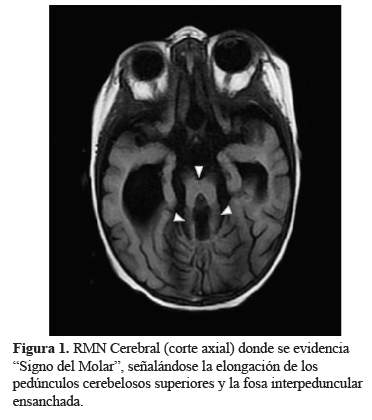

El Síndrome de Joubert fue descrito por primera vez (1), como un trastorno clínico, genético y radiológicamente heterogéneo (2). Se estudiaron dos familias con un fenotipo similar, agenesia del vermis cerebeloso, hiperpnea episódica neonatal, movimientos oculares anormales, ataxia, retraso mental y encefalomeningocele occipital en uno de ellos. En 1977, Boltshauser e Isler describieron esta afección denominándose Síndrome de Joubert - Boltshauser cuyo diagnóstico incluye los hallazgos clínicos con imágenes características en cortes axiales de resonancia magnética, el denominado “signo del molar”(Figura 1) (3), además de la agenesia vermiana (4,5).

Si bien en el SJ existe una gran variabilidad en la presentación clínica, su hallazgo fundamental en la resonancia cerebral es la presencia de distintos grados de displasia cerebelosa con una característica en común, el “Signo del Molar” (“SM”) del mesencéfalo. En algunos casos puede presentarse de forma extensa y difusa, con hemisferios cerebelosos y vermis rudimentarios, localizados dentro de una fosa posterior pequeña, con el IV ventrículo en comunicación con una gran cisterna magna, y con el tronco encefálico hipoplásico y el cuerpo calloso agenésico. En otros casos la displasia es más pronunciada y puede acompañarse de diferentes grados de hipoplasia de los hemisferios cerebelosos, así como de aumento de tamaño del IV ventrículo. Por último, la hipoplasia cerebelosa puede ser asimétrica, asociada a la afectación preferente de un hemisferio cerebeloso y a encefalocele parietooccipital. Puede, también, tratarse de una aplasia total de vermis cerebeloso asociada a profundas alteraciones de la unión cervicomedular, incluyendo ausencia completa de la decusación piramidal, displasia de los núcleos olivar y paraolivar, e hipoplasia del núcleo gracilis y del fascículo solitario (10).